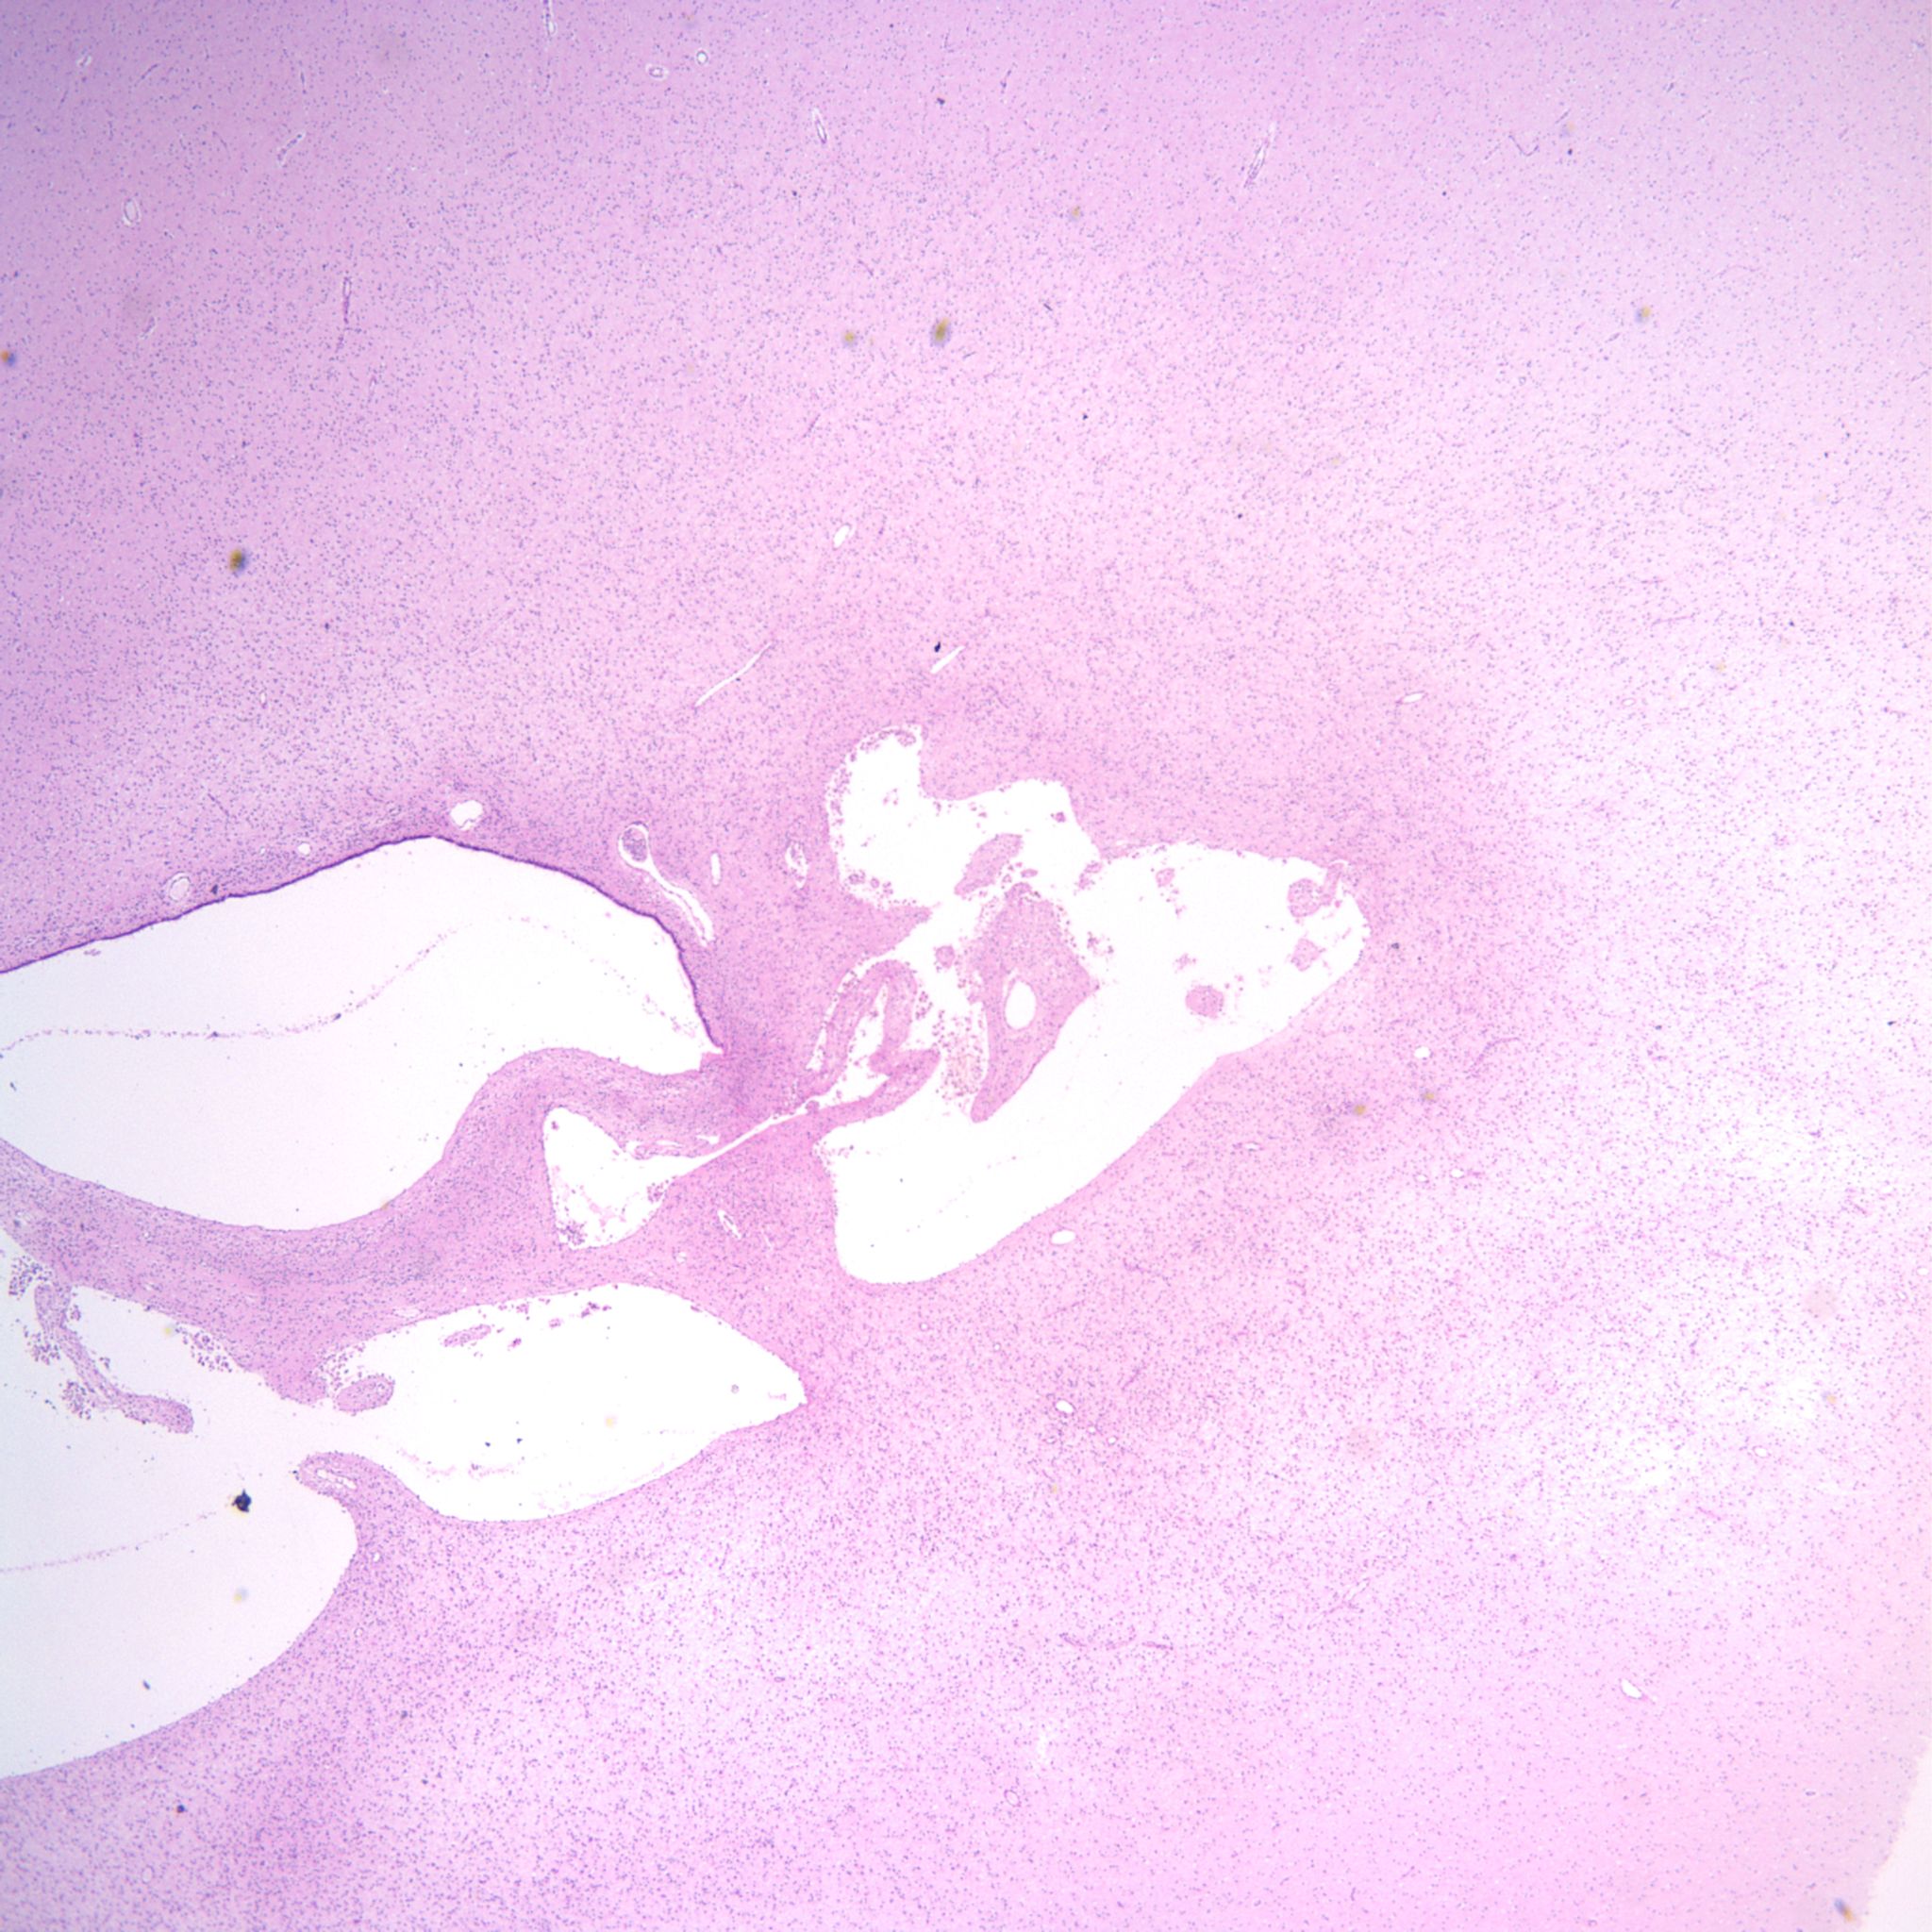

Intraventricular hemorrhage is usually the result of germinal matrix hemorrhage or hemorrhage from periventricular leukomalacia. The germinal matrix exists from early gestation to term as a reserve of immature cells that will become neurons and glia. The amount decreases after 33 weeks of gestation. The risk of IVH synchronously decreases with the maturation of the germinal matrix. Hemorrhage in this soft embryonic appearing tissue with prominent thin-walled vessels may occur in response to various risks including hypoxia, cytokines, or suddenly changing vascular pressures. Most hemorrhages are identified after birth. However, intraventricular hemorrhage can be found in previable fetuses at autopsy (Fig 1).

Grossly, in the intact brain, blood in the ventricles often seeps and pools around the base of the brain (Fig 2).